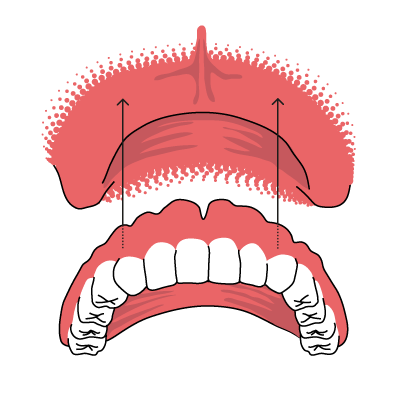

Totalprothese